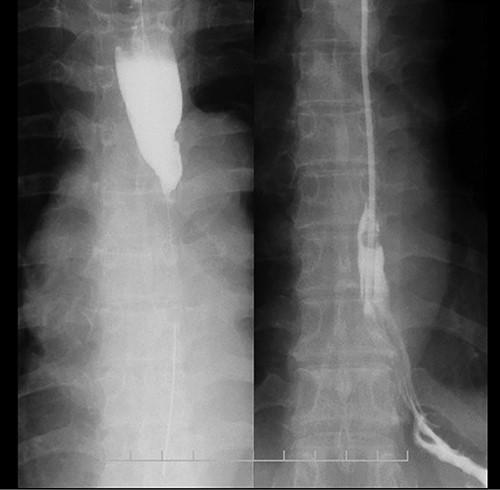

Upper gastrointestinal series showing the stomach; there were no specific findings in the stomach.

Preoperative computed tomography (CT) and barium meal studies were performed. The CT findings showed circumferential wall thickening with infiltrative change at the middle of the intrathoracic esophagus, with luminal dilation of the oral side of the stenotic esophagus (Figs 2, 3). The barium meal study showed no abnormal findings in the stomach (Fig. 4). Thoracoscopic esophagectomy was performed with the patient in the semi-prone position, followed by esophageal reconstruction using a gastric tube with the patient in the supine position. The operation was started with bilateral lung ventilation using a single-lumen endotracheal tube. A four-port thoracoscopic technique was used as follows: an observation port with a 10-mm scope was placed at the ninth intercostal space at the line of the inferior scapular angle, and two 5-mm ports and one 12-mm port for the intrathoracic procedures were placed at the third, fifth and seventh intercostal spaces, respectively, at the posterior axillary line (Fig. 5). Pneumothorax was created using 10 mmHg of CO2 to deflate the lung to achieve a better operative field. The pleura and connective tissue around the thoracic esophagus showed severe inflammatory and fibrotic changes. In particular, the middle thoracic esophagus was strongly adherent to the arch of the azygos vein and the tracheal bifurcation.